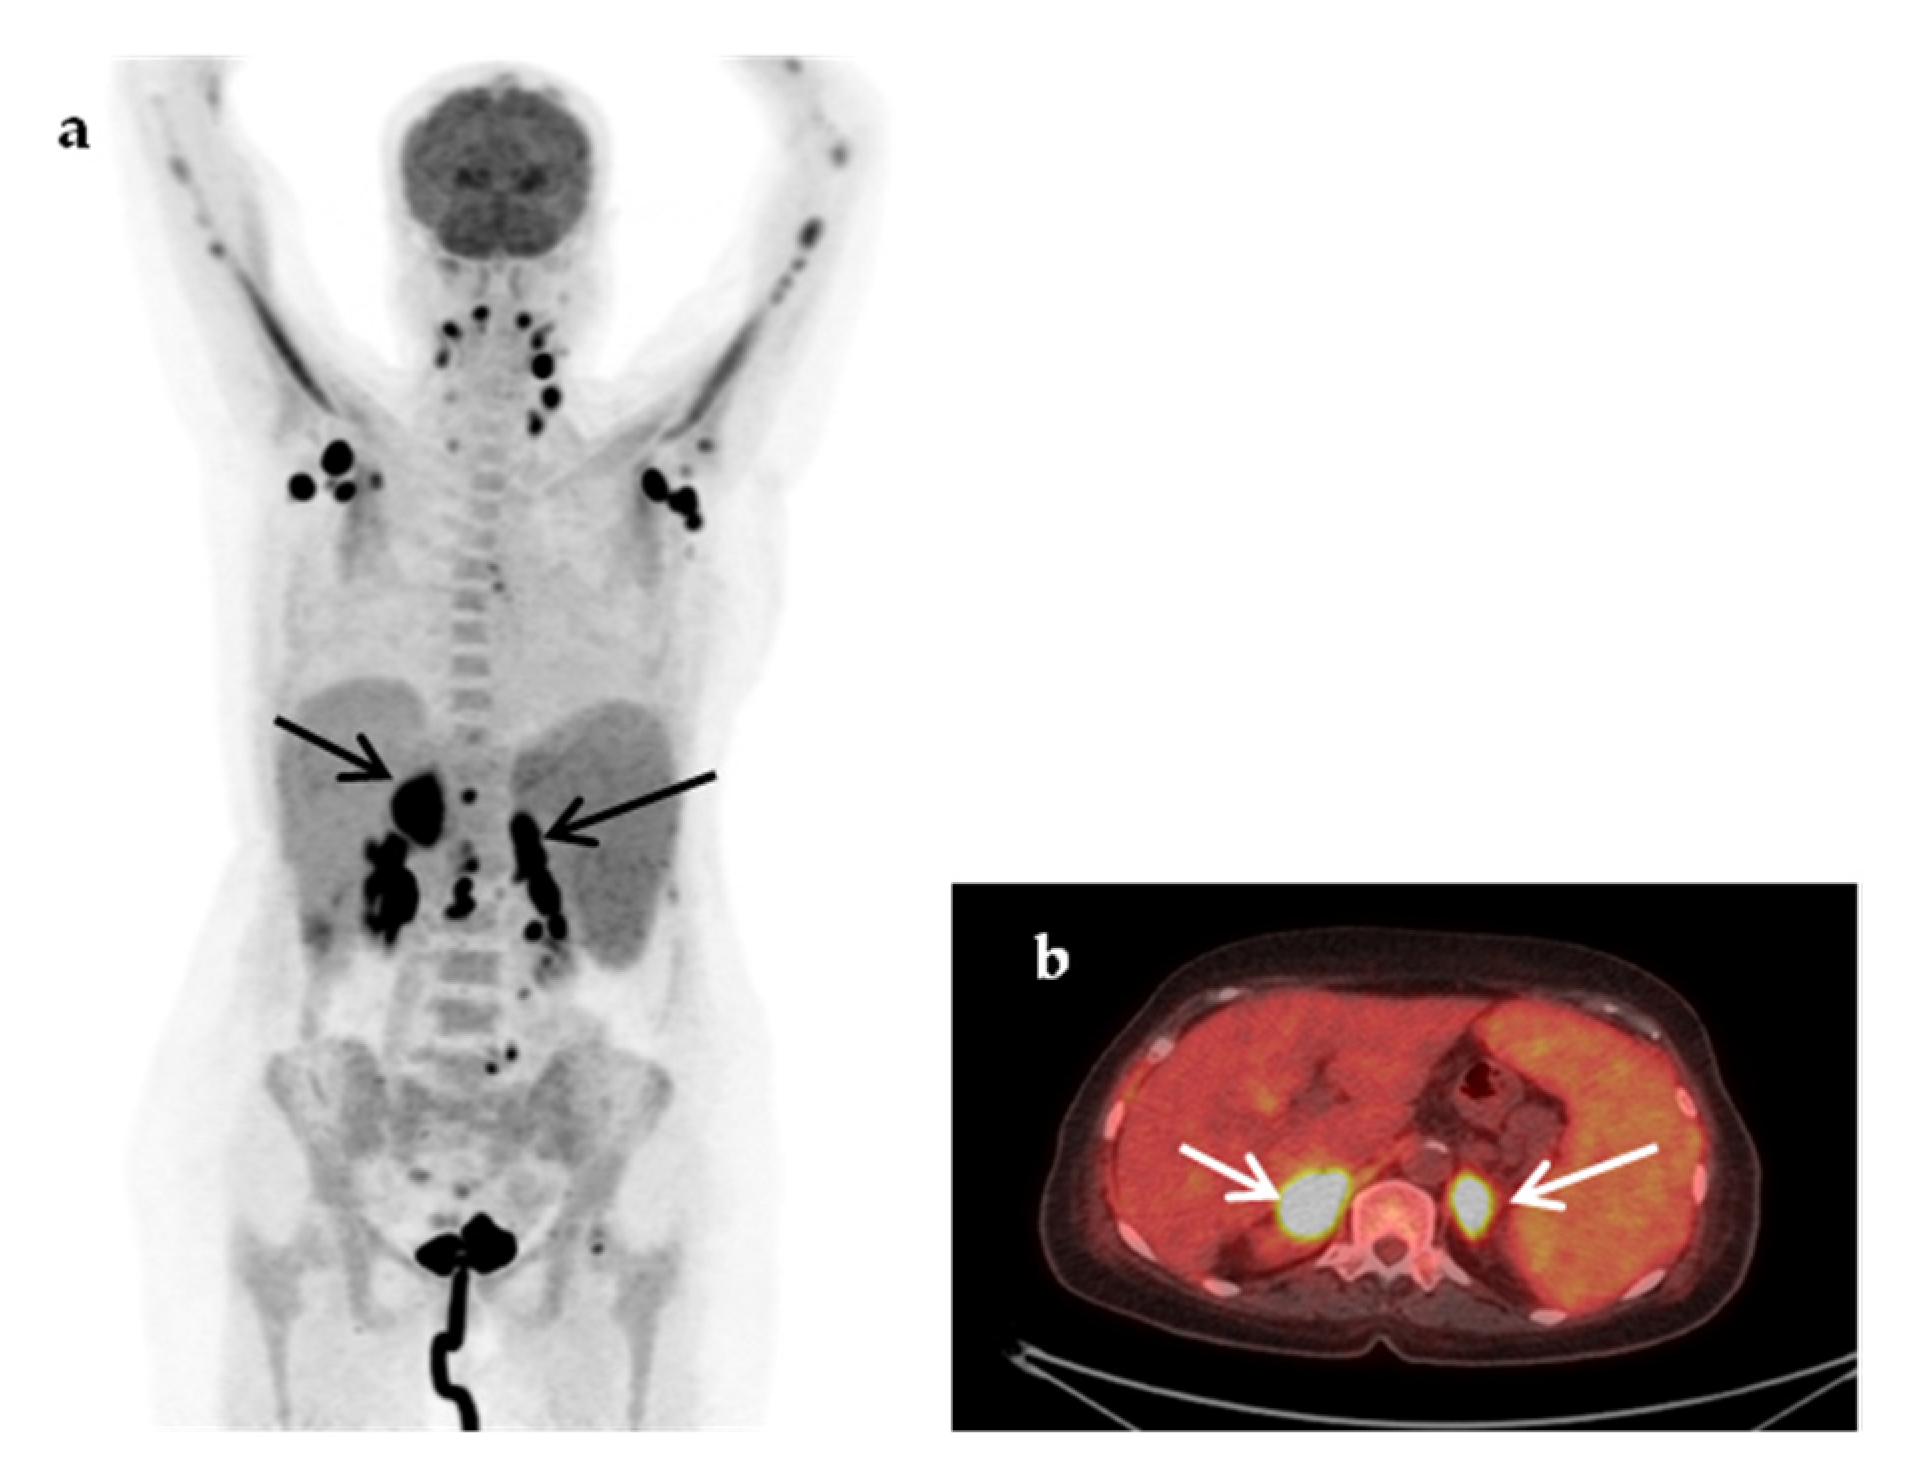

| Non-infectious Inflammatory diseases (NIID) | 11 (22%) |

| Large vessel vasculitis/Takayasu’s arteritis | 3 |